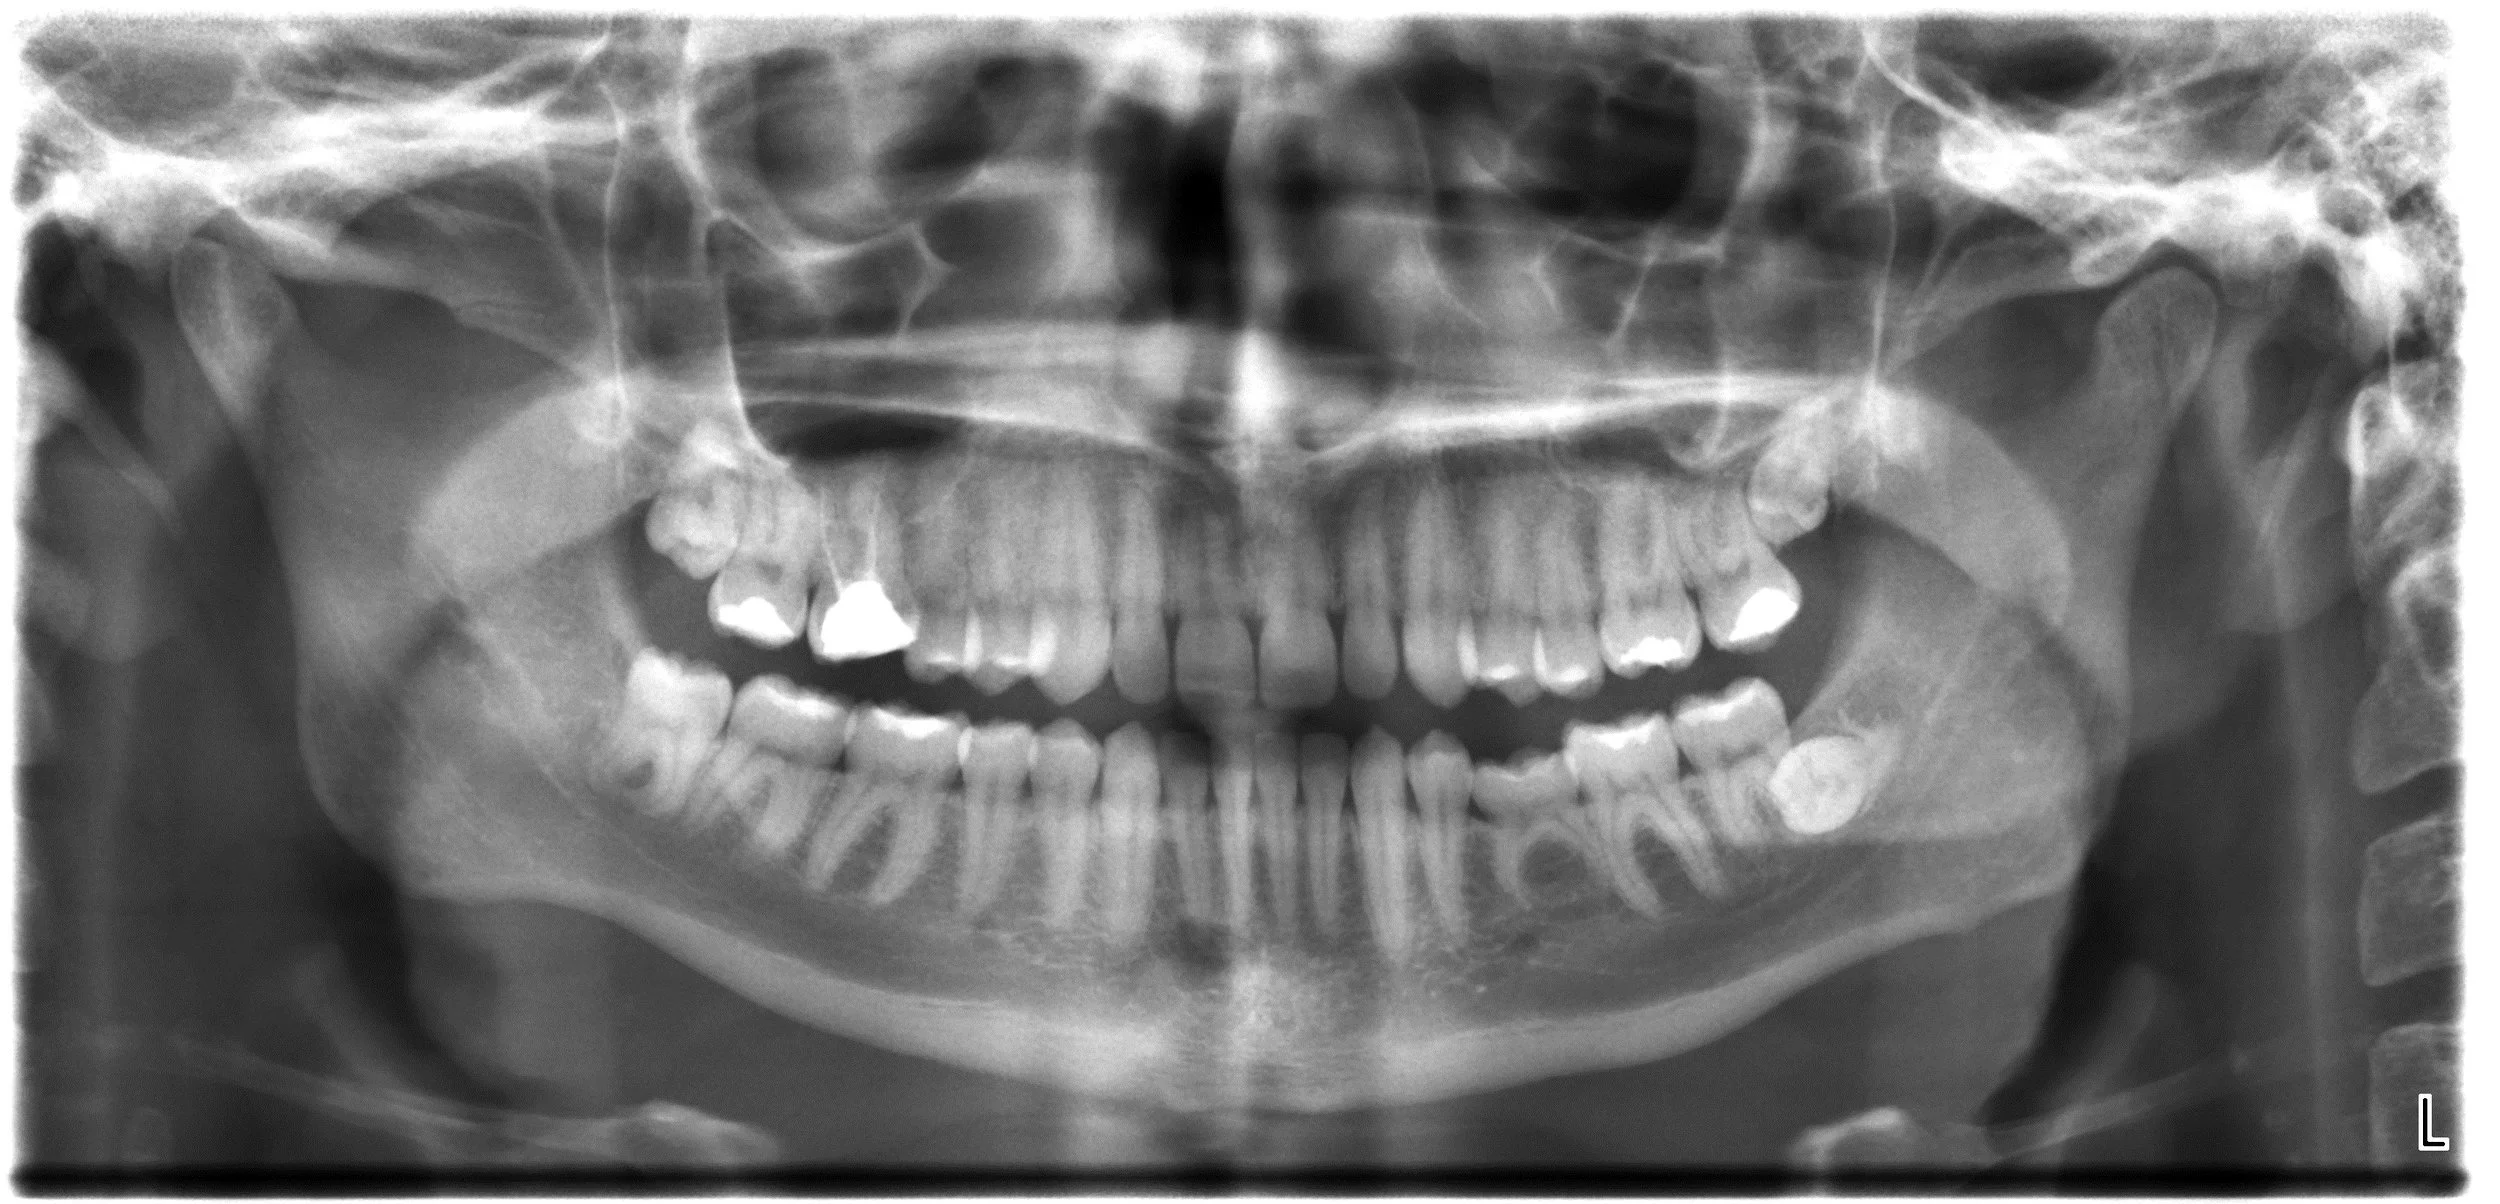

Sudden impact and chronic grinding are common causes of tooth damage. Miller Dental Health Centre offers options to both prevent and cope with these problems.